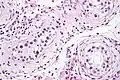

| Intratubular germ cell neoplasia. H&E stain. | |

GCNIS is not palpable, and not visible on macroscopic examination of testicular tissue. Microscopic examination of affected testicular tissue most commonly shows germ cells with enlarged hyperchromatic nuclei with prominent nucleoli and clear cytoplasm. These cells are typically arranged along the basement membrane of the tubule, and mitotic figures are frequently seen. The sertoli cells are pushed toward the lumen by the neoplastic germ cells, and spermatogenesis is almost always absent in the affected tubules. Pagetoid spread of GCNIS into the rete testis is common. Immunostaining with placental alkaline phosphatase (PLAP) highlights GCNIS cell membranes in 95 percent of cases. OCT3/4 is a sensitive and specific nuclear stain of GCNIS.[3]

ITGCN. H&E stain.